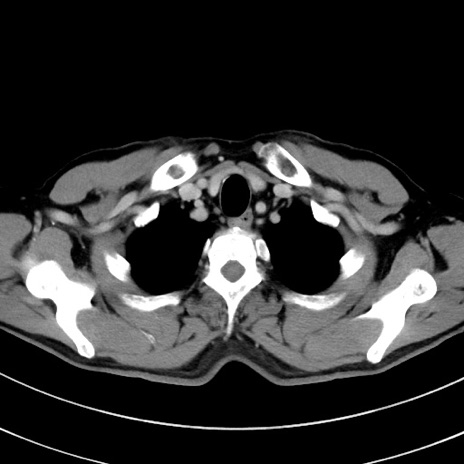

症例8(横断像)

【症例】 60歳代男性

【主訴】 黒色吐物

【現病歴】 4日前から嘔気自覚、2日前の朝食後にも嘔気あり、自分で手で嘔吐反射起こし嘔吐したところ血が混ざっていたため受診。

【既往歴】 5年前汎発性腹膜炎を伴う急性虫垂炎で手術、高血圧、前立腺肥大症、高脂血症

【身体所見】 腹部正中に手術癩痕あり 腹部平坦・軟圧痛なし膨満感あり

【データ】WBC 8400、CRP 4.54